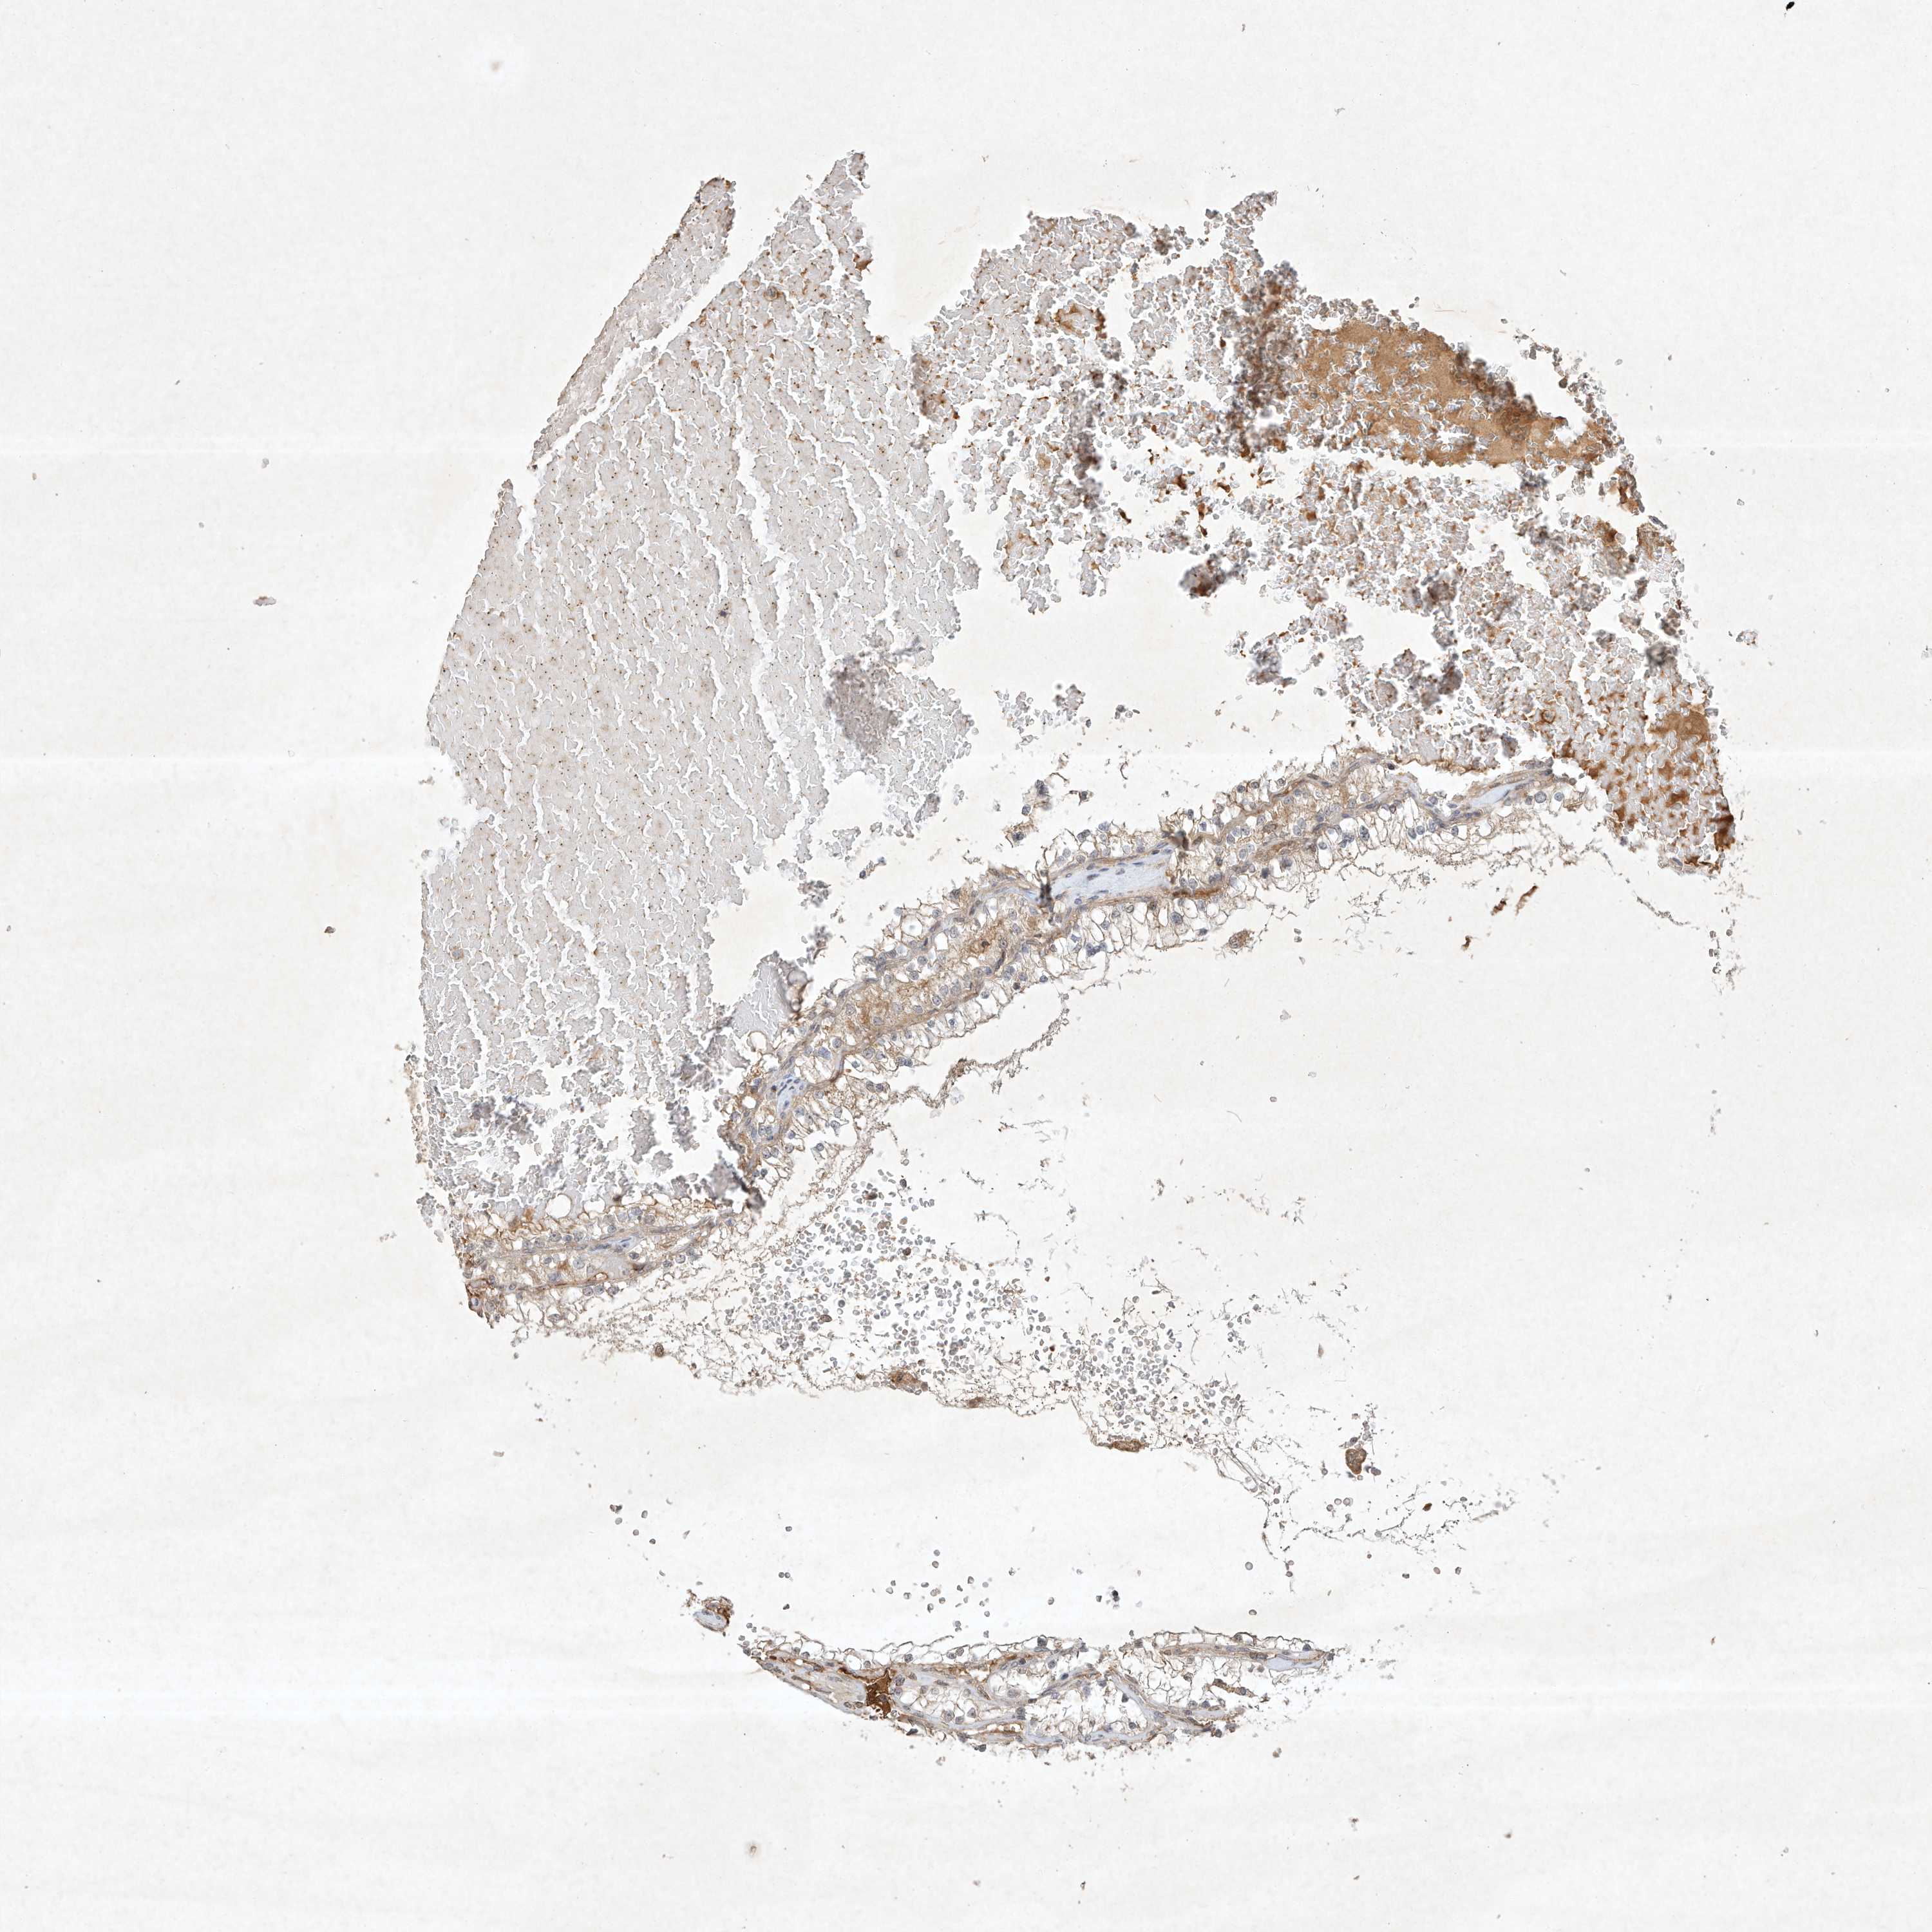

KIDNEY RENAL CLEAR CELL CARCINOMA (VALIDATION) - Interactive survival scatter ploti

The Survival Scatter plot shows the clinical status (i.e. dead or alive) for all individuals in the patient cohort, based on the same data that underlies the corresponding Kaplan-Meier plots. Patients that are alive at last time for follow-up are shown in blue and patients who have died during the study are shown in red.

The x-axis shows the expression levels (FPKM) of the investigated gene in the tumor tissue at the time of diagnosis. The y-axis shows the follow-up time after diagnosis (years). Both axes are complimented with kernel density curves demonstrating the data density over the axes. The top density plot shows the expression levels (FPKM) distribution among dead (red) and alive patients (blue). The right density plot shows the data density of the survived years of dead patients with high and low expression levels respectively, stratified using the cutoff indicated by the vertical dashed line through the Survival Scatter plot. This cutoff is automatically defined based on the FPKM cutoff that minimizes the p-score. The cutoff can be changed by dragging the vertical line or by entering a cutoff value in the square labeled "Current cut-off".

Under the Survival Scatter plot the p-score landscape (black curve; left axis) is shown together with dead median separation (red curve; right axis). Dead median separation is the difference in median mRNA expression between patients who have died with high and low expression, respectively. It is calculated as follows: median FPKM expression of dead patients with high expression - median FPKM expression of dead patients with low expression. This is intended to aid the user in visually exploring custom cutoffs and the associated p-scores and dead median separation.

Individual patient data is displayed and can be filtered by clicking on one or more of the category buttons on the top of the page. Categories describing expression level and patient information include: high, low, alive, dead, female, male and tumor stages. The scale of the x-axis can be toggled between linear and log-scale by clicking on the "x log" button. Mouse-over function shows TCGA ID, patient information and mRNA expression (FPKM) for each patient.

& Survival analysisi

Kaplan-Meier plots summarize results from analysis of correlation between mRNA expression level and patient survival. Patients were divided based on level of expression into one of the two groups "low" (under cut off) or "high" (over cut off). X-axis shows time for survival (years) and y-axis shows the probability of survival, where 1.0 corresponds to 100 percent.

BTRC is not prognostic in Kidney Renal Clear Cell Carcinoma (validation)

Best expression cut offi

Based on the FPKM value of each gene, patients were classified into two groups and association between prognosis (survival) and gene expression (FPKM) was examined. The best expression cut-off refers the FPKM value that yields maximal difference with regard to survival between the two groups at the lowest log-rank P-value. Best expression cut-off was selected based on survival analysis .

When clicking on this number, the vertical dashed line indicating cut-off, the interactive survival plot, and the Kaplan-Meier curve will be adjusted to show results based on the best expression cut-off.

: 8.56

TCGA RNA samplesi

RNA-seq data is reported as average FPKM (number Fragments Per Kilobase of exon per Million reads), generated by the The Cancer Genome Atlas (TCGA) .

Normal distribution across the dataset is visualized with box plots, shown as median and 25th and 75th percentiles. Points are displayed as outliers if they are above or below 1.5 times the interquartile range. FPKM values of the individual samples are presented next to the box plot.

Average pTPM 7.3

Number of samples 100